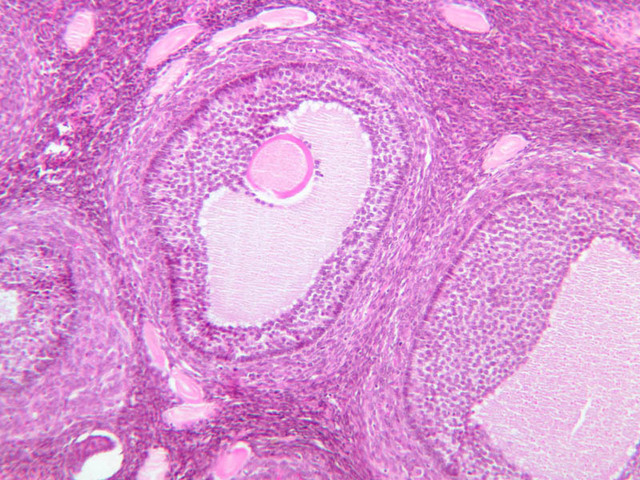

The ovary is a somewhat oval and slightly flattened organ situated near the fimbriated end of the uterine tube (B-94, monkey ovary, H&E [1x, 1x]; B-95, monkey ovary, H&E [1x-labeled, 1x]; B-96, monkey ovary and tube, H&E [1x]; B-54, H&E [1x, 1x]). Its exposed surface is covered by a mesothelial sheet of squamous or cuboidal epithelium. Just deep to this is an ill defined area of dense fibrous connective tissue referred to as the tunica albuginea (B-96 [2.5x-labeled, 10x-labeled, 20x, 40x]).

The ovary has two major regions – the cortex and the medulla. The cortex is the broad peripheral area containing follicles in various stages of development, whereas the medulla is the more central area displaying profiles of large blood vessels. These blood vessels gain entrance via the mesovarium. The division between the cortex and medulla is indistinct. In the cortex, stromal cells occupy the areas between the follicles. These cells are closely packed, fusiform (spindle shaped), and have the potential to differentiate into a specialized component of the maturing follicle (theca folliculi).

Secondary Follicle

• Early (vesicular stage)

• With continued granulosa cell proliferation, spaces filled with fluid (liquor folliculi) appear within this layer.

• Later (antral stage)

• Continued follicular enlargement occurs and the irregular spaces within the granulosa layer merge to form a single crescentric cavity, the antrum.

• Those granulosa cells immediately surrounding the zona pellucida become columnar and are referred to as the corona radiata.

• The theca folliculi begins to segregate itself into two distinct layers.

Secondary Follicles (B-94 [2.5x, 10x-labeled, 20x] [2.5x, 10x, 20x]; B-96 [2.5x, 10x-labeled, 20x, 40x] [2.5x, 10x, 20x])

Mature (Graafian) Follicle

At maximum size, follicles will bulge from the ovarian surface and occupy the full thickness of the cortex. The oocyte is displaced to one side of the antrum where it is surrounded by a thickening of granulosa cells. This stalk-like thickening is referred to as the cumulus oophorus. A distinct basal lamina separates the granulosa cells from the theca. The theca has segregated itself into the theca interna and the theca externa. The theca interna is adjacent to the basal lamina, highly vascular and consists of secretory cells. The theca externa is connective tissue that merges with the adjacent stroma. Mature (Graafian) Follicle (slide B-94 [2.5x, 10x, 20x-labeled] [10x, 20x, 40x] [10x, 20x, 40x])